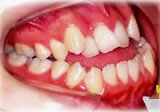

開咬症例

初診時年齢○○歳。前歯部での咬合不全を主訴に来院。

骨格性開咬と診断し、外科的処置を併用して治療。

治療前 治療後

右側面 右側面 右側面